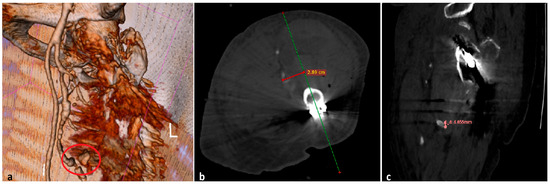

2. Case Presentation